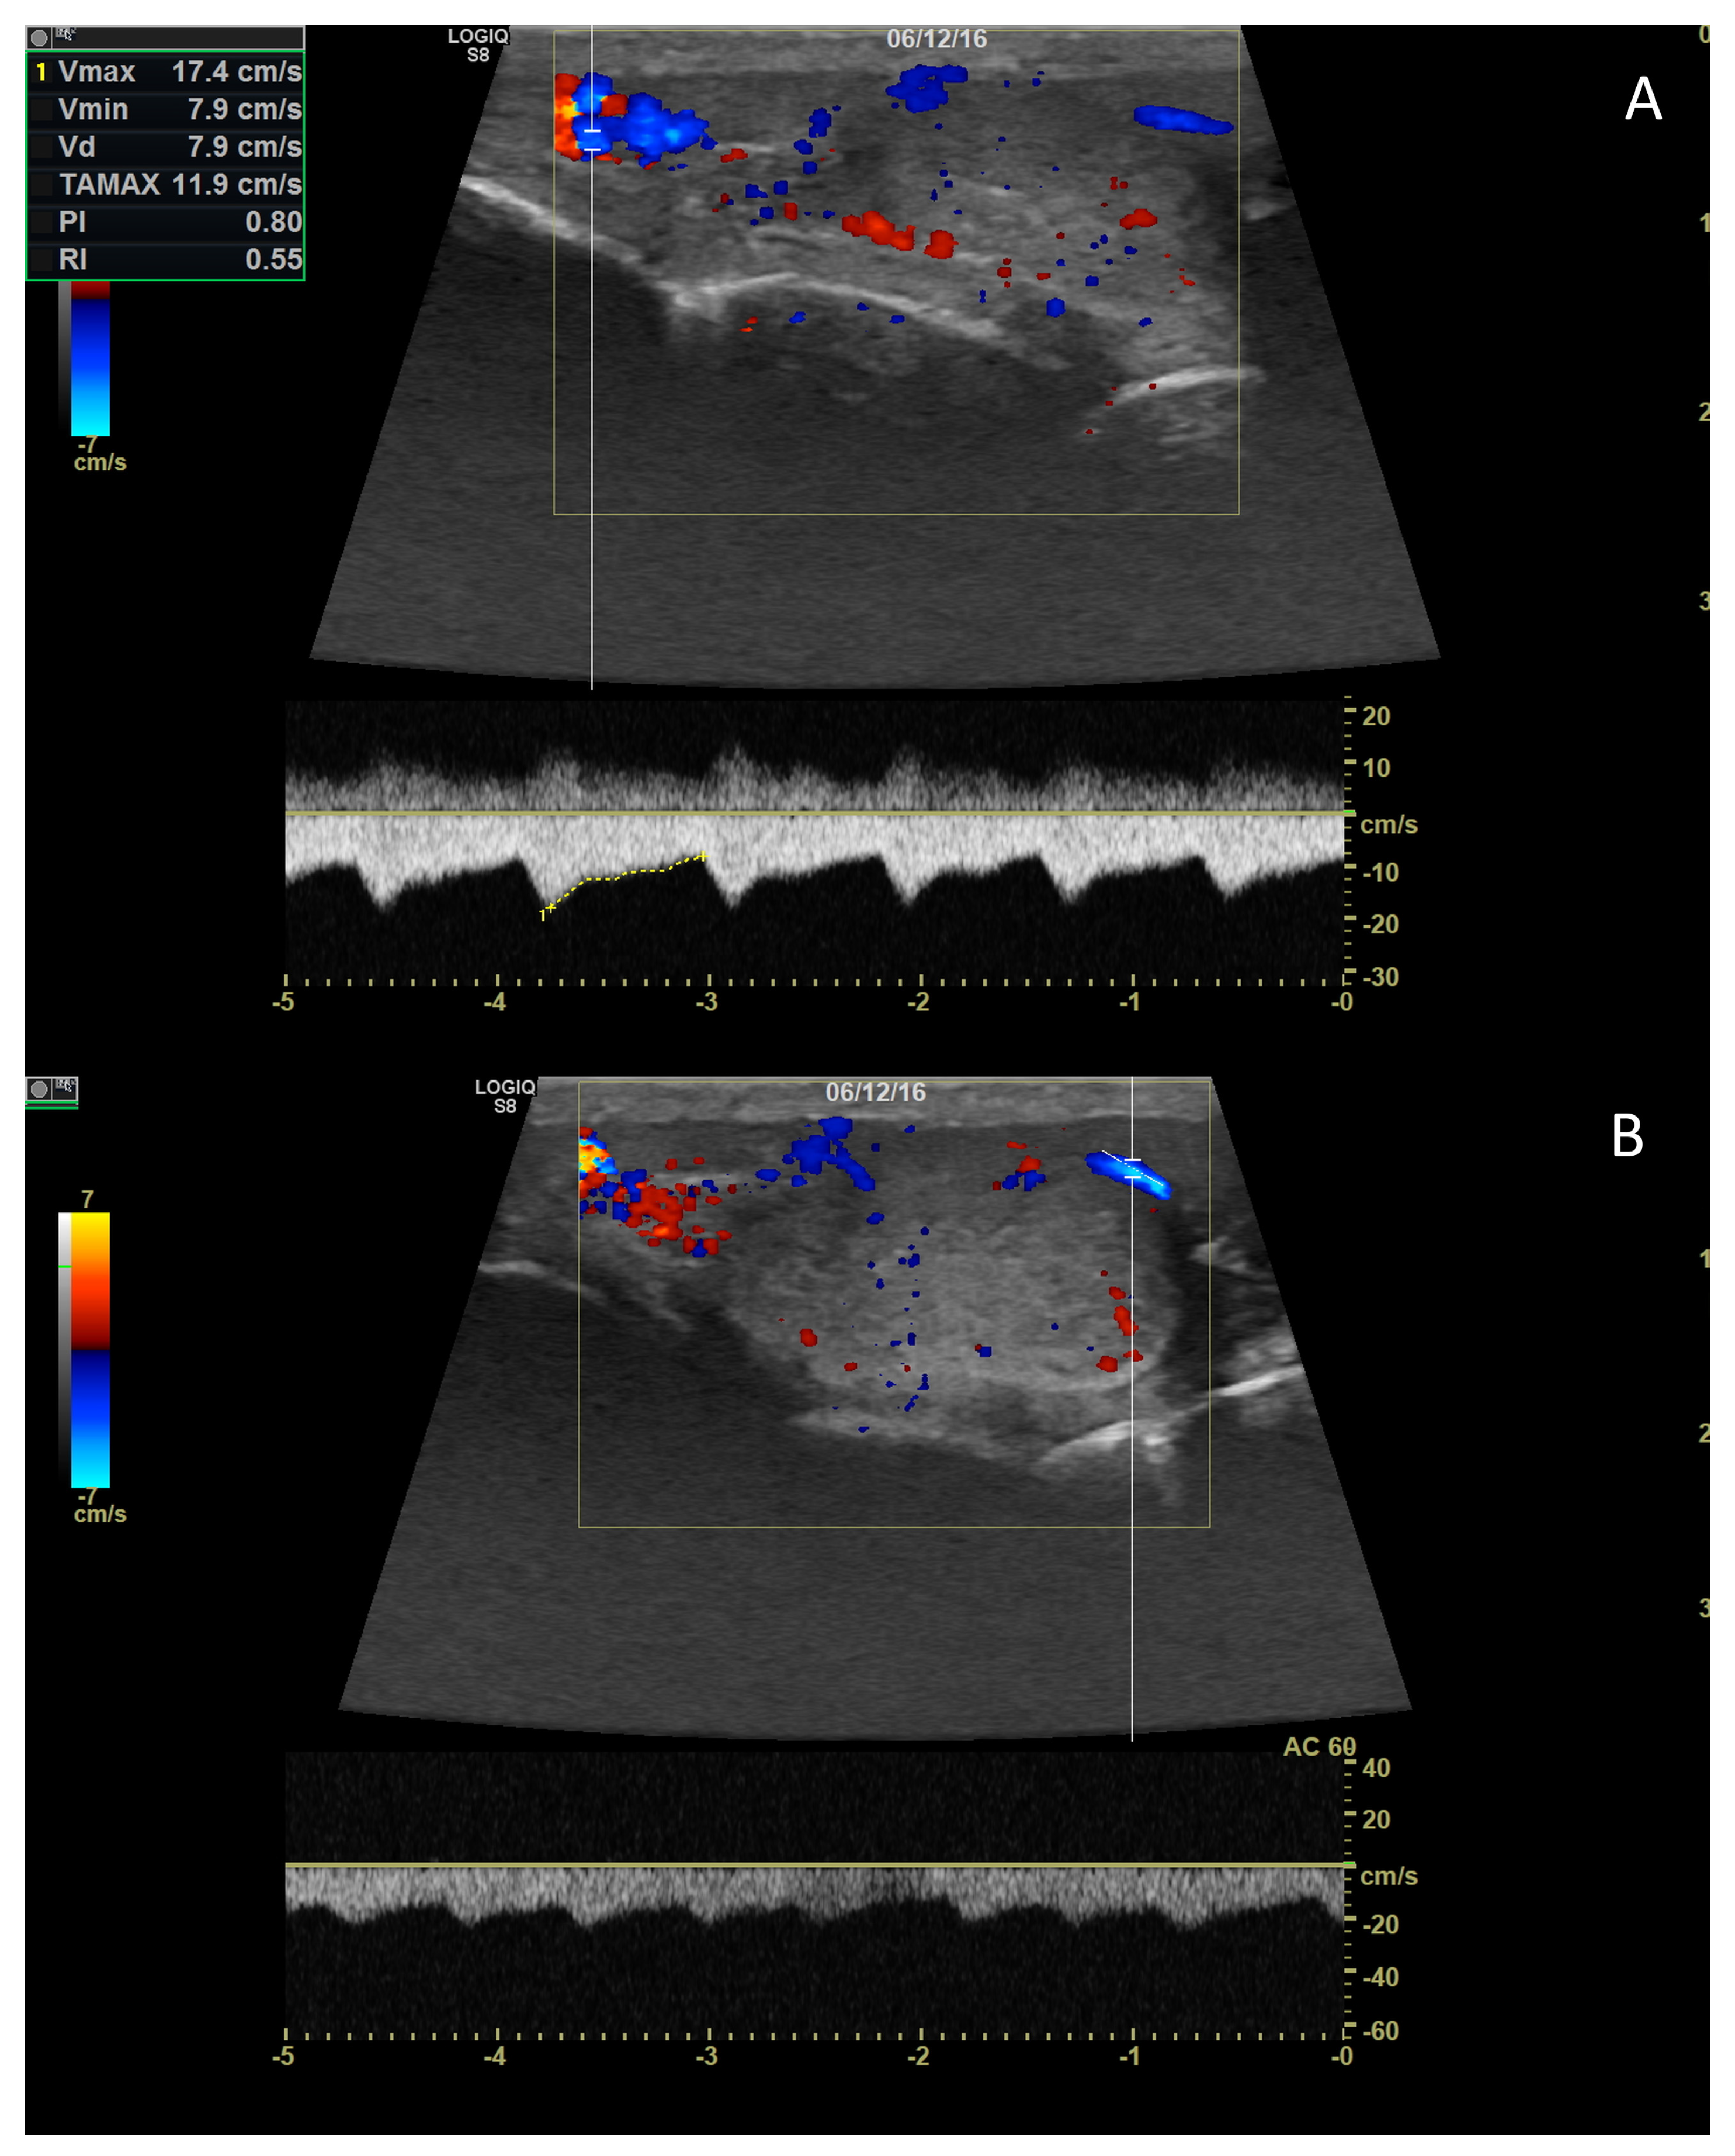

3. Grey-Scale Ultrasonography

3.3. Normal Findings

3.4. Abnormal Findings

3.4.1. Intratesticular Diseases